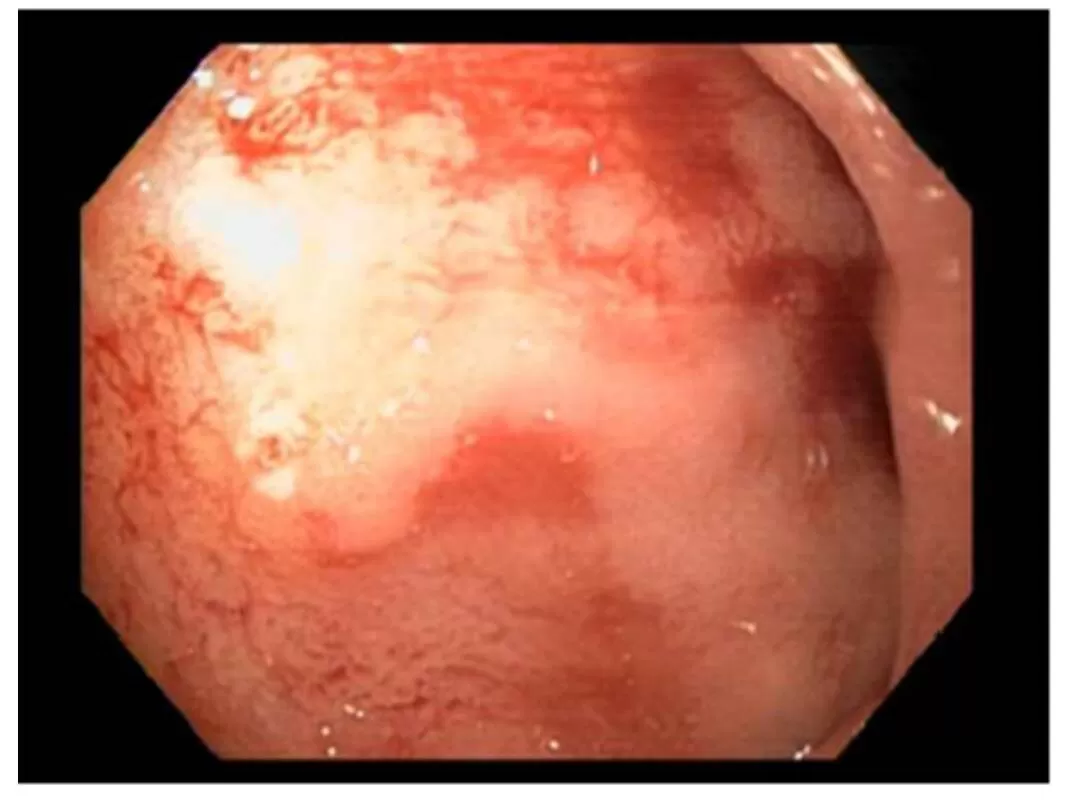

We presented a case of A 54 year old Hispanic male with recurrent episodes of abdominal distension and up to three previous hospitalizations with a diagnosis of partial bowel obstruction that resolved with conservative management. The physical examination revealed overweight (BMI= 28 Kg/m2). A colonoscopy was performed with the discovery of three hyperplastic polyps, and barium small bowel radiographic studies showed folds thickening of jejunal and ileal loops (Fig. 1).

Figure 1:  Small bowel radio graphics with barium. Morphological changes of jejunal bowel loops are shown that explain the symptoms of partial intestinal obstruction experienced by the patient